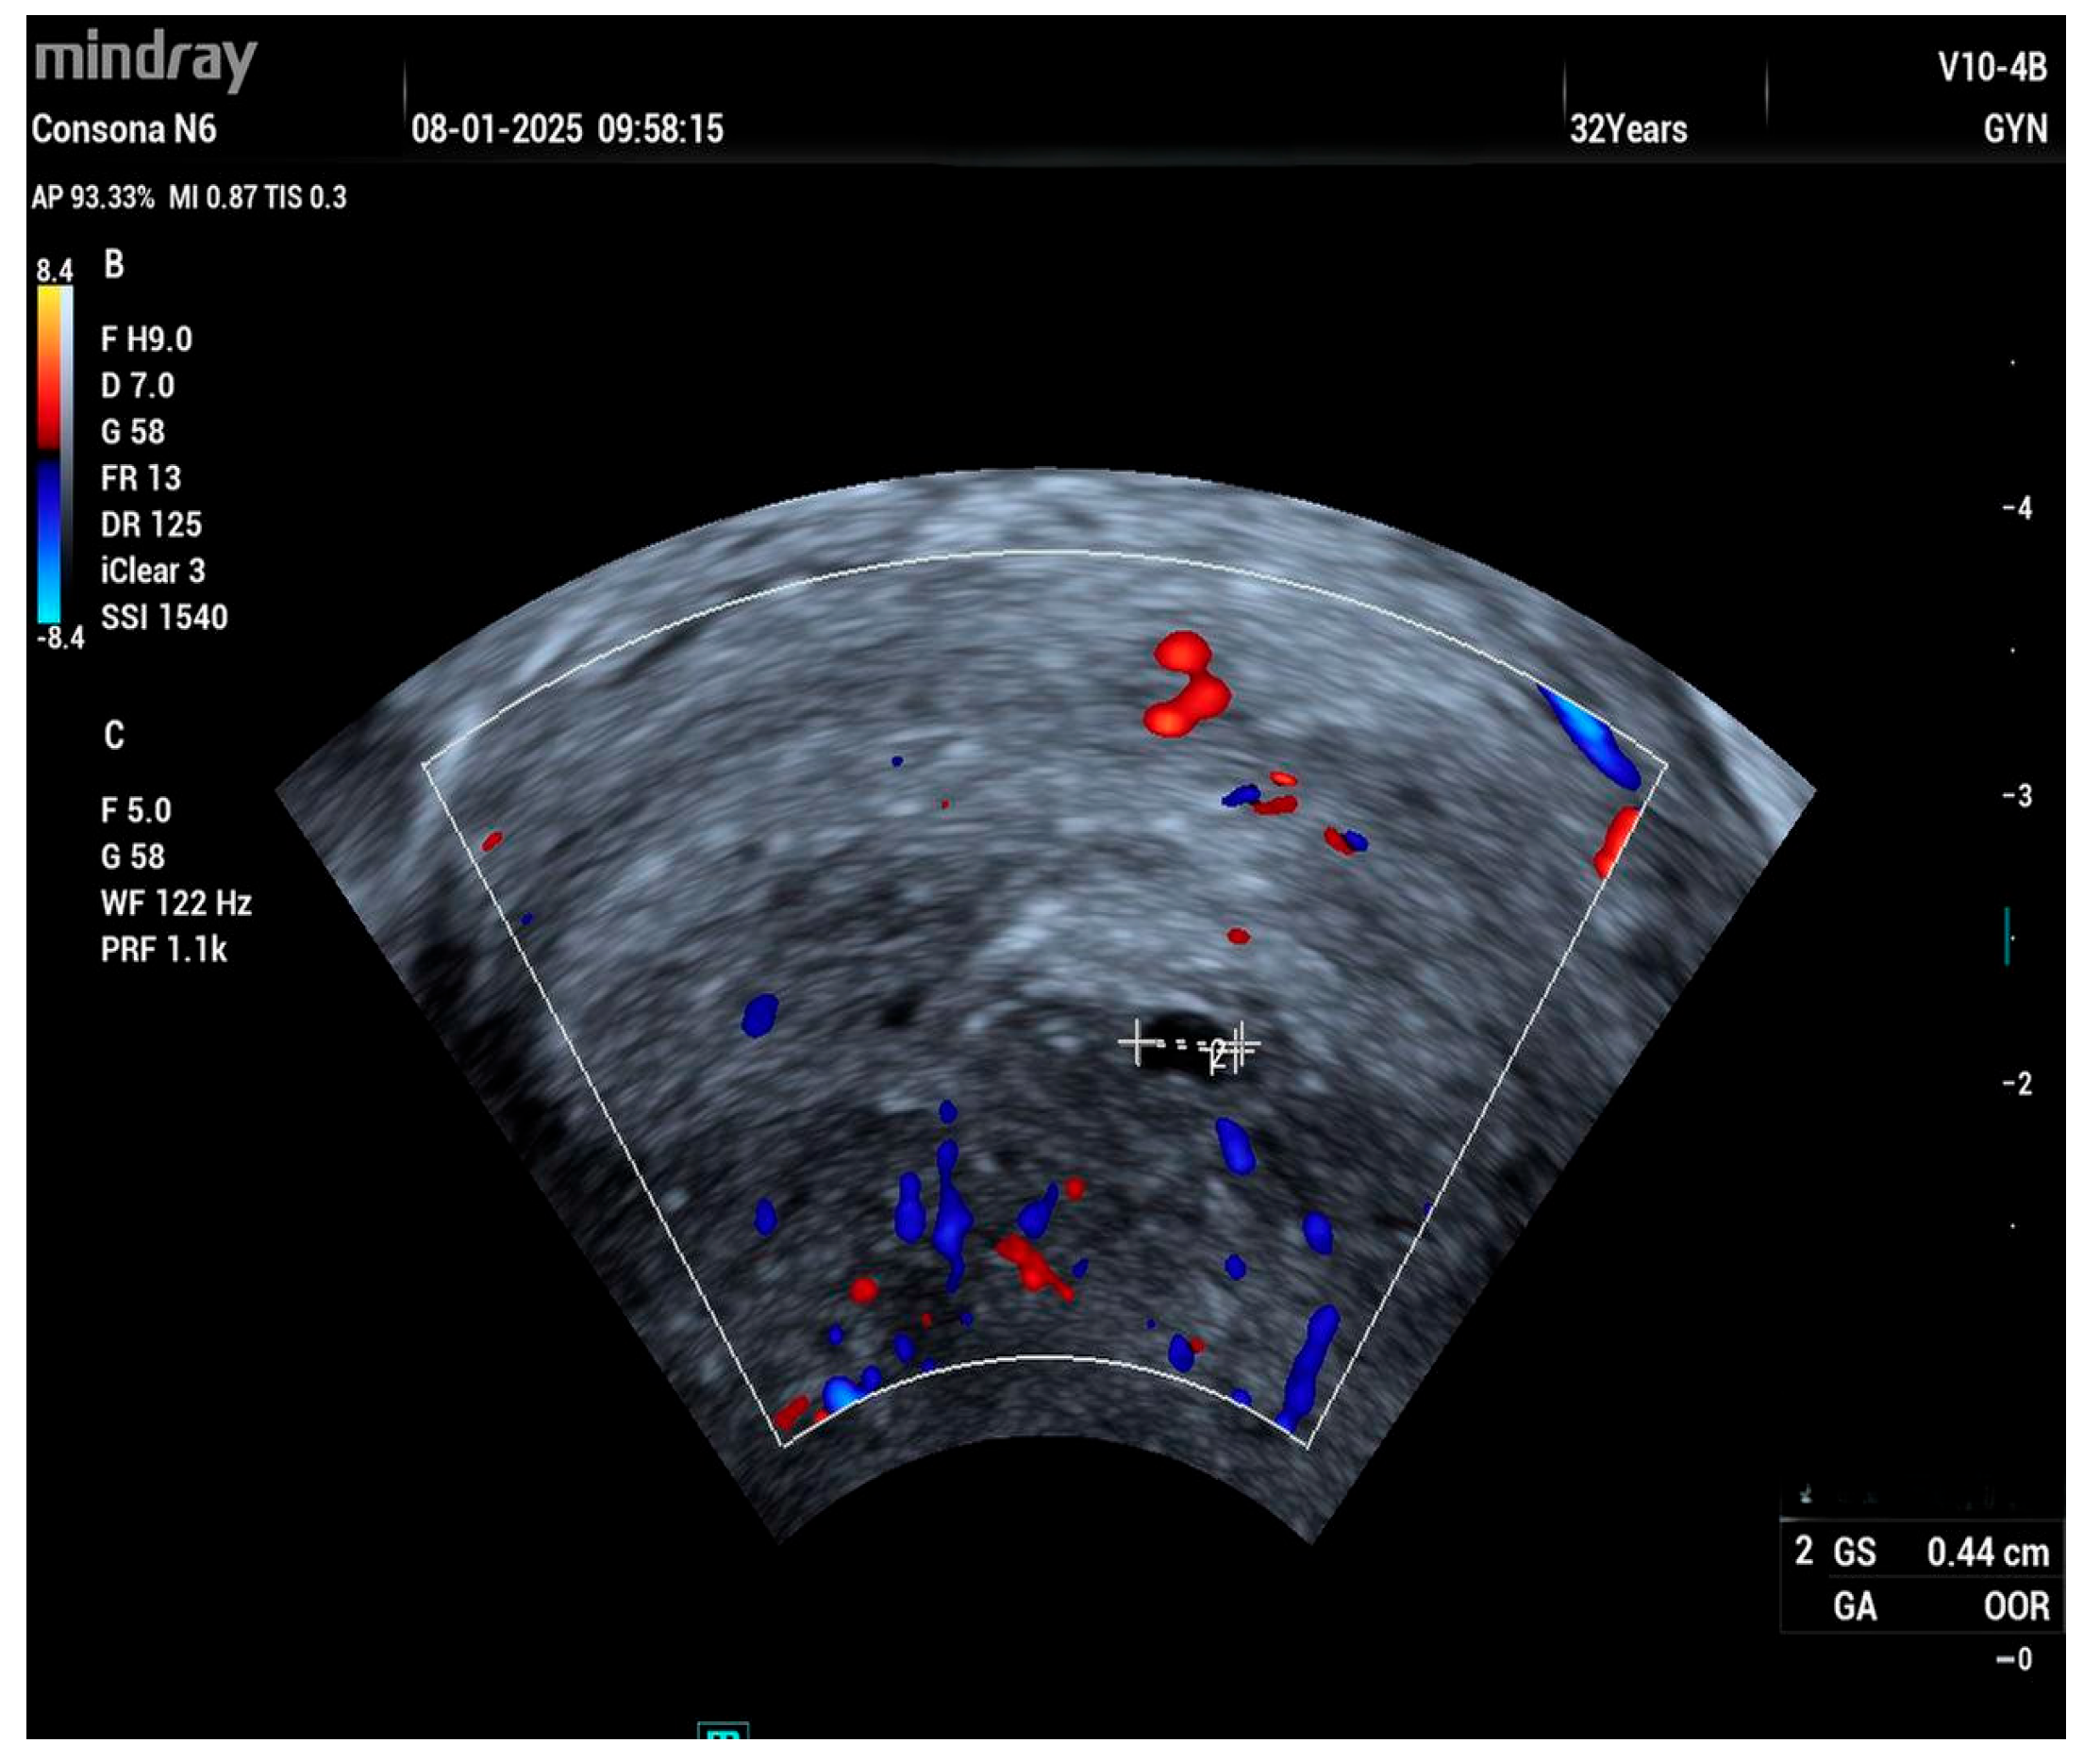

A 32-year-old woman, gravida 1 para 0, was referred to our clinic at six weeks gestation with a suspected ectopic pregnancy. She had previously undergone hysteroscopic surgery to remove a uterine septum 3 years ago. A transvaginal ultrasound showed a 0.44 mm pseudogestational sac in the uterus (Figure 1).

Figure 1. Pseudo sac in the uterine cavity.

Compared to electrosurgical instruments and other laser systems, the Ho:YAG laser is associated with a shallower depth of tissue penetration, resulting in less thermal injury and reduced collateral damage [27,28,29,30]. This is particularly beneficial in procedures such as hysteroscopic metroplasty, where minimizing the risk of uterine perforation is critical, especially in women desiring future fertility. The limited lateral thermal spread also supports faster endometrial healing and may help reduce the risk of postoperative intrauterine adhesions (Figure 1) [31].